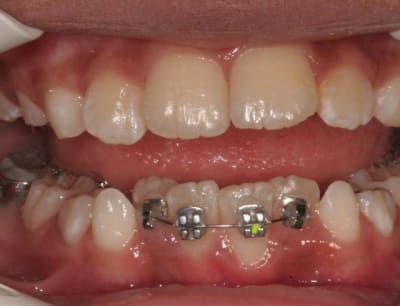

En postant cette contention, je m’adressait surtout à ceux qui ont font régulièrement et qui ont, comme moi, des petits Pbs. j’ai été un peu concis, je vais mieux expliquer pour ceux qui seraient tentés d’en faire

un composite d’obturation est très bien toléré, (comme dirait Dancha)

le Pb. est le surcontour.

surcontour d’1 Bk. ou d’une contention sur une face de la dent

plus ce surcontour sera important, plus la plaque se déposera en dessous et sera difficile à éliminer. ici, ce qui me plait est que le surcontour est très fin, mais il existe quand mm. et demande un bon contrôle de plaque.

souvent le composite de recouvrement s’use et la trame des rubans de fibres esthétiques apparaît, les fibres ayant tendance à " rebiquer ", ce qui est un piège à plaque

(je sais, il y en des nouveaux)

dans le cas présenté, lorsque le composite de recouvrement s’usera, ce sera du métal (or) qui sera mis à nu. ceux qui ont vu des stéllites en or dans une bouche comprendront l’avantage sur une fibre en partie effilochée.

et ce qui ne gâte rien, je le trouve très facile à mettre en place, plus facile qu’un ruban, et aussi esthétique

3°) phase

contention

@+ Bjc